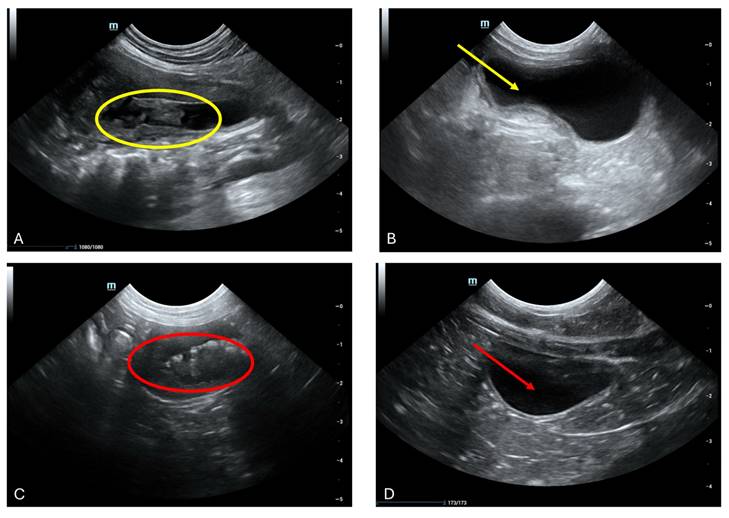

Cystitis, a prevalent pathology affecting the feline urinary bladder, frequently necessitates meticulous evaluation. While overt manifestations may be absent in cases of acute or mild cystitis, chronic presentations often unveil notable alterations in bladder wall integrity, with reductions in echogenicity indicative of edematous changes (Fig. 3 A and C). Notably, wall thickening, a hallmark of cystitis, predominantly localizes to the cranioventral aspect of the bladder but can extend diffusely in severe instances (Fig. 3 A yellow circle and C red circle). It is imperative to exercise meticulous attention to bladder filling status during assessments to mitigate misinterpretation of a structurally intact yet incompletely filled bladder as pathologically thickened. Furthermore, the presence of intraluminal material, such as inflammatory debris, warrants meticulous scrutiny (Fig. 3 A yellow circle and 3 C red circle). Following a therapeutic intervention utilizing fADSCs-derived exosomes, subsequent ultrasound evaluations conducted one month post-treatment revealed a promising restoration of normal bladder architecture in seven feline subjects (Fig. 3 B yellow arrows and D red arrows). Despite this encouraging outcome, definitively attributing the etiology of the condition remained elusive. Consequently, uncertainty persists regarding whether cystitis served as a primary instigating factor or emerged as a sequela to the underlying pathology. These findings underscore the intricate interplay between cystitis and underlying disease processes, underscoring the imperative for continued research to unravel their nuanced dynamics.

Aberrant intraluminal formations resembling pseudomembranous cystitis, albeit lacking conclusive histological confirmation, were discerned. (a) Ultrasonographic scrutiny of the urinary bladder in a 9-year-old male neutered domestic shorthair cat unveiled marked thickening and irregularities along the cranial bladder wall, concomitant with the presence of intraluminal material (Yellow circle). (b) Following a month of therapeutic intervention, the bladder presented devoid of luminal contents, with a discernibly thin and non-inflamed mucosal lining, indicative of the amelioration of previously identified irregularities (Yellow arrow).(c) Cross-sectional ultrasonographic assessment of the urinary bladder in a 2-year-old female feline unveiled the presence of a dense, highly echogenic sediment within the bladder cavity (red circle), resulting in notable shadowing artifacts during imaging sessions. (d) A 15-day interim follow-up ultrasonographic examination of the aforementioned feline addressing the abnormalities previously detected.

The findings from the study on Feline Idiopathic Cystitis (FIC) treatment with exosomes and subsequent ultrasonographic analysis reveal promising outcomes. Notably, a significant proportion of treated cats exhibited resolution of symptoms within a relatively short timeframe, with seven out of ten showing improvement after just 15 days of treatment. Ultrasonographic observations before and after treatment demonstrated marked changes in bladder morphology, including the disappearance of intraluminal material and restoration of mucosal integrity, indicative of successful therapeutic intervention. Although histological confirmation of observed abnormalities was lacking, the consistent improvement across cases underscores the potential efficacy of exosome therapy in managing FIC-related urinary tract abnormalities.